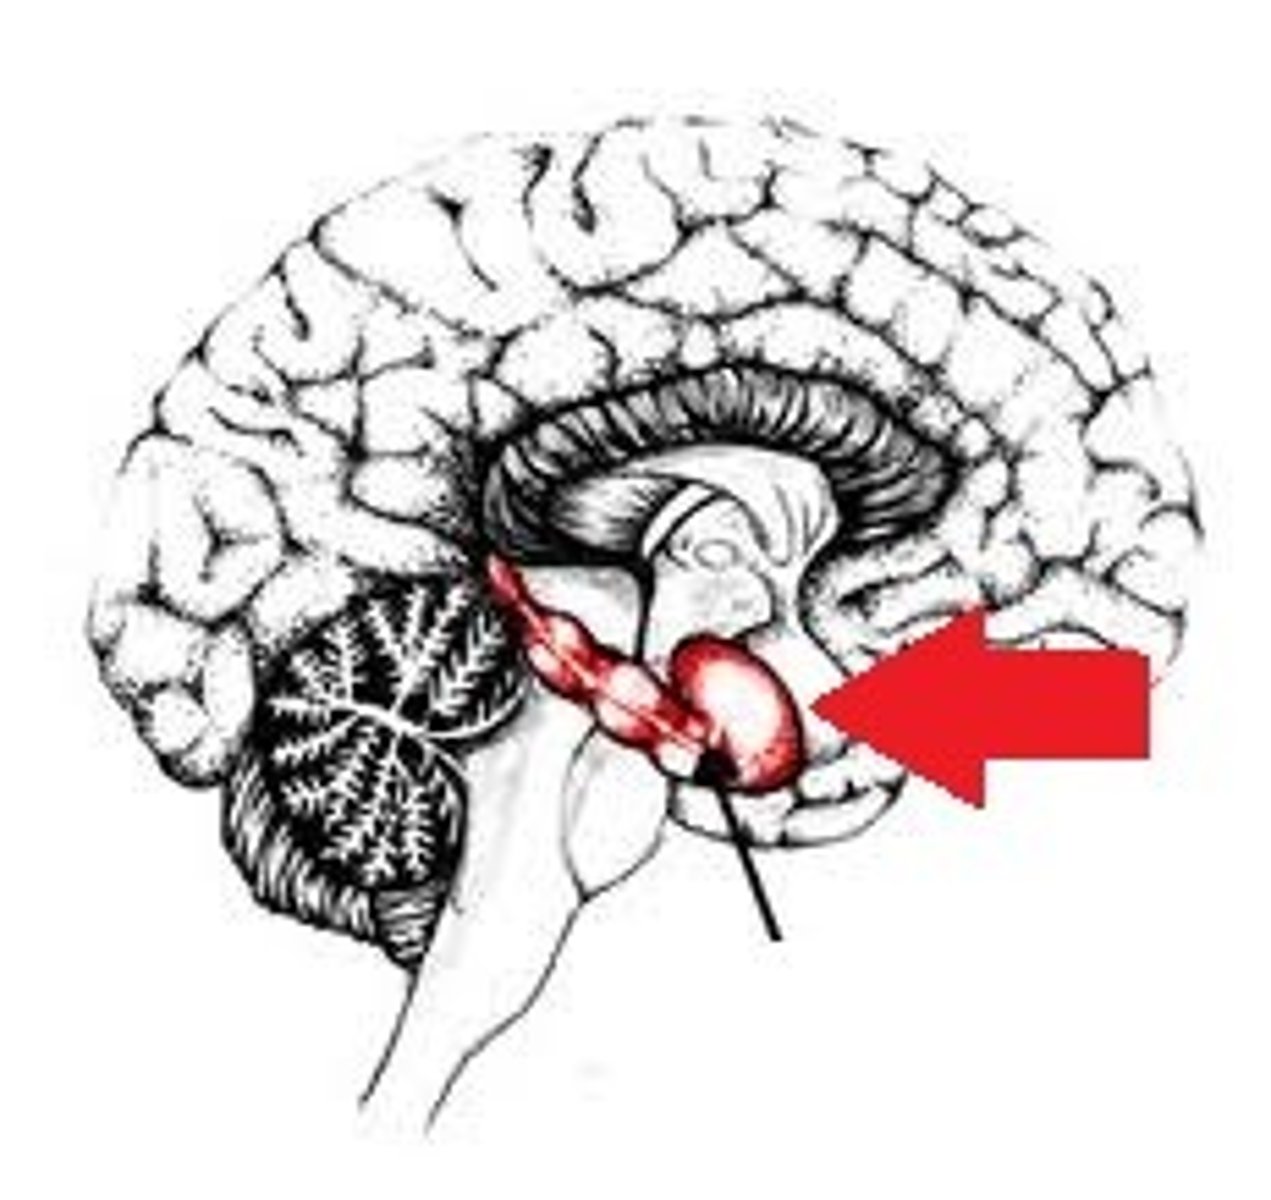

Dopaminergic pathway

knowt flashcard image

Ventral tegmental area (VTA)

Midbrain structure where dopamine is produced: associated with mood, reward, and addiction

<p>Midbrain structure where dopamine is produced: associated with mood, reward, and addiction</p>